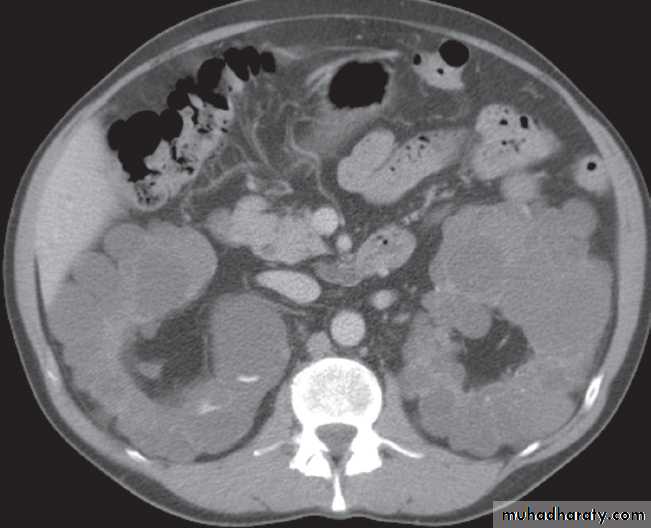

There are many varieties of cystic renal disease varying from simple cysts, which may be single or multiple, to complex renal dysplasias. The most frequent complex dysplasia encountered in clinical practice is autosomal dominant polycystic kidney disease.Renal agenesis